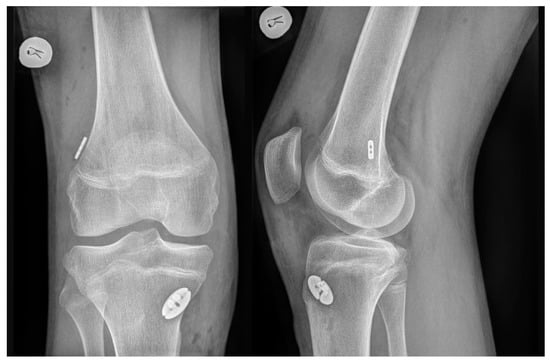

For all autografts, the same transepiphyseal tunnel drilling technique was performed. A 4 mm-diameter full femoral tunnel was drilled along with a 2-to-2.5 cm deep femoral socket, according to the graft diameter. Full tibial tunnel was drilled according to graft diameter. Both HT and QT autografts were fixed in the knee joint with cortical suspensory devices on both the femur and the tibia (TightRope RT and ABS TightRope, Arthrex (Naples, FL, USA)). A post-operative X-ray examination was performed after each ACLR to confirm the position of the implants (Figure 2).

Figure 2.

Post-operative X-ray examination confirming the position of the implants.